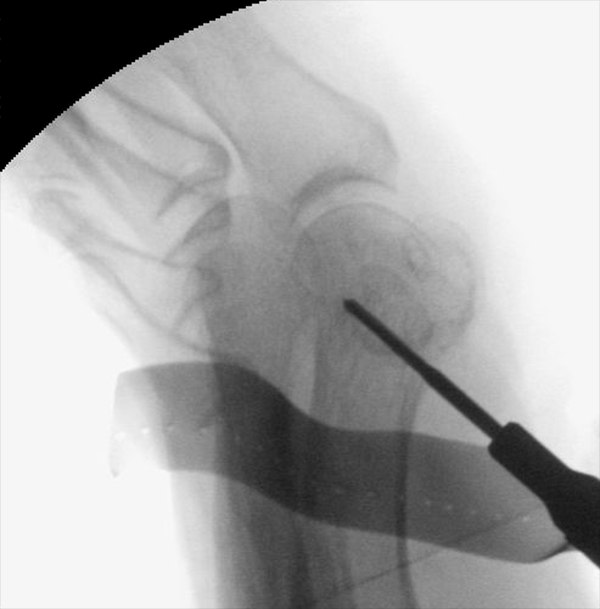

Zum Lesen der Bildbeschreibung und zur Vollansicht bitte die Bilder anklicken.

• Positionierung des Bildwandlers: 90° Winkel zum Os metatarsale I. Benötigt wird die Durchleuchtung des Vorfußes a.p., seitlich und schräg.

Operationstechnik

Der von Isham/Reverdin beschriebenen minimal invasiven Technik zur Korrektur einer Hallux valgus Deformität liegen 4 Operationsschritte zu Grunde:

2. Subcapitale intraartikuläre Osteotomie

3. Laterales Release

4. Akin Osteotomie der Großzehengrundphalanx

Die Folge der Operationsschritte sollte strikt von 1. - 4. erfolgen, da ansonsten die mediale Closing Wedge Osteotomie bei vorzeitigem lateralem Release und/oder Akin Osteotomie nicht geschlossen werden kann. Nach der von Isham beschriebenen Originaltechnik finden Implantate keine Anwendung, zur Sicherung und besseren Fixation können osteosynthetische Verfahren angewandt werden (siehe auch Fehler, Gefahren und Komplikationen).